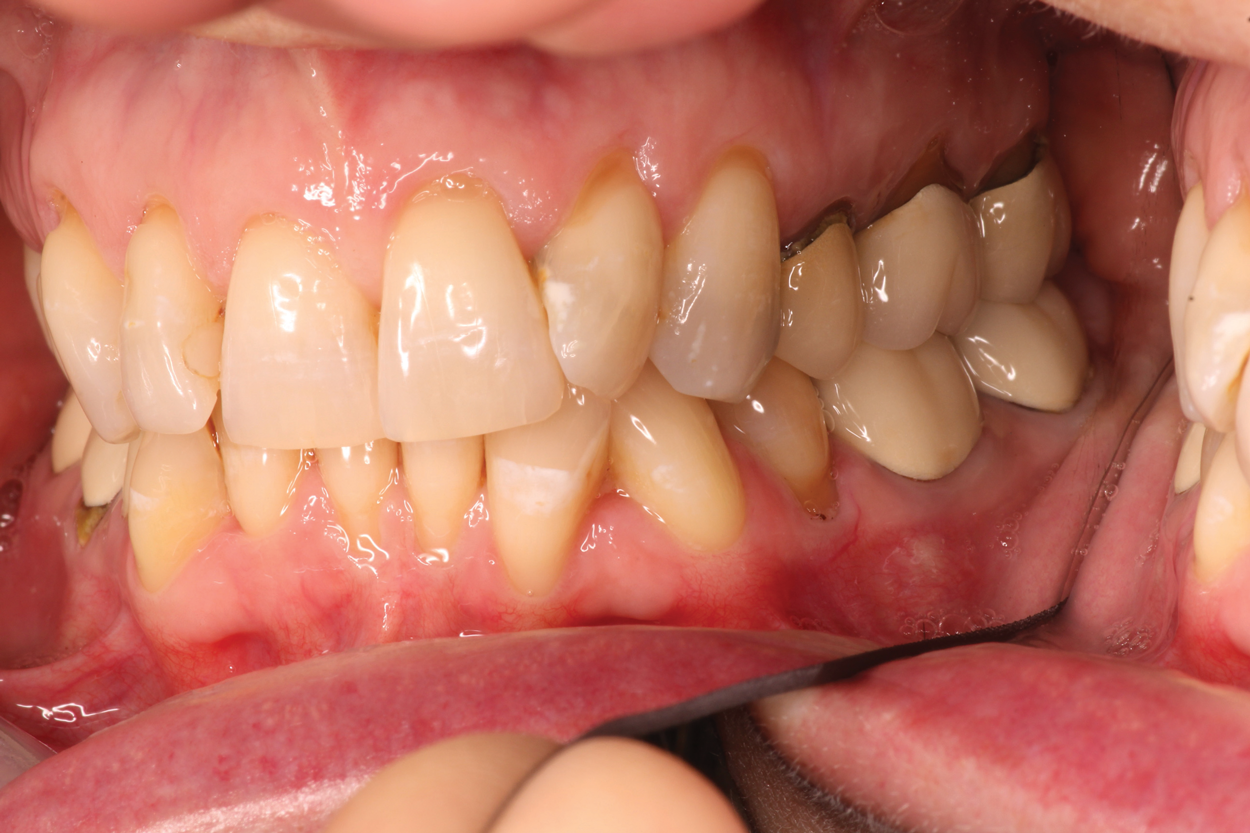

A 56-year-old female patient required an extensive treatment plan, including multiple crowns and fillings in each quadrant. She was able to complete treatment only in stages. By the time one quadrant was completed, she began to have pain on the mesial of tooth No. 20 (Figure 1 and Figure 2). Because the patient had no more dental benefits for the year, she needed to alleviate the sensitivity and prevent further problems between appointments. The doctor recommended SDF to stave off the sensitivity she was experiencing and to prevent growth of the lesion. Silver diamine fluoride was placed during a restorative appointment, and her sensitivity and pain subsided. When she returned a month later for her hygiene visit, she stated her pain had returned. A second SDF treatment was administered, which prevented the pain from returning a third time, until her restorative treatment could resume.

(3.) Patient presented with sensitivity for 6 months on tooth No. 18.

Figure 3